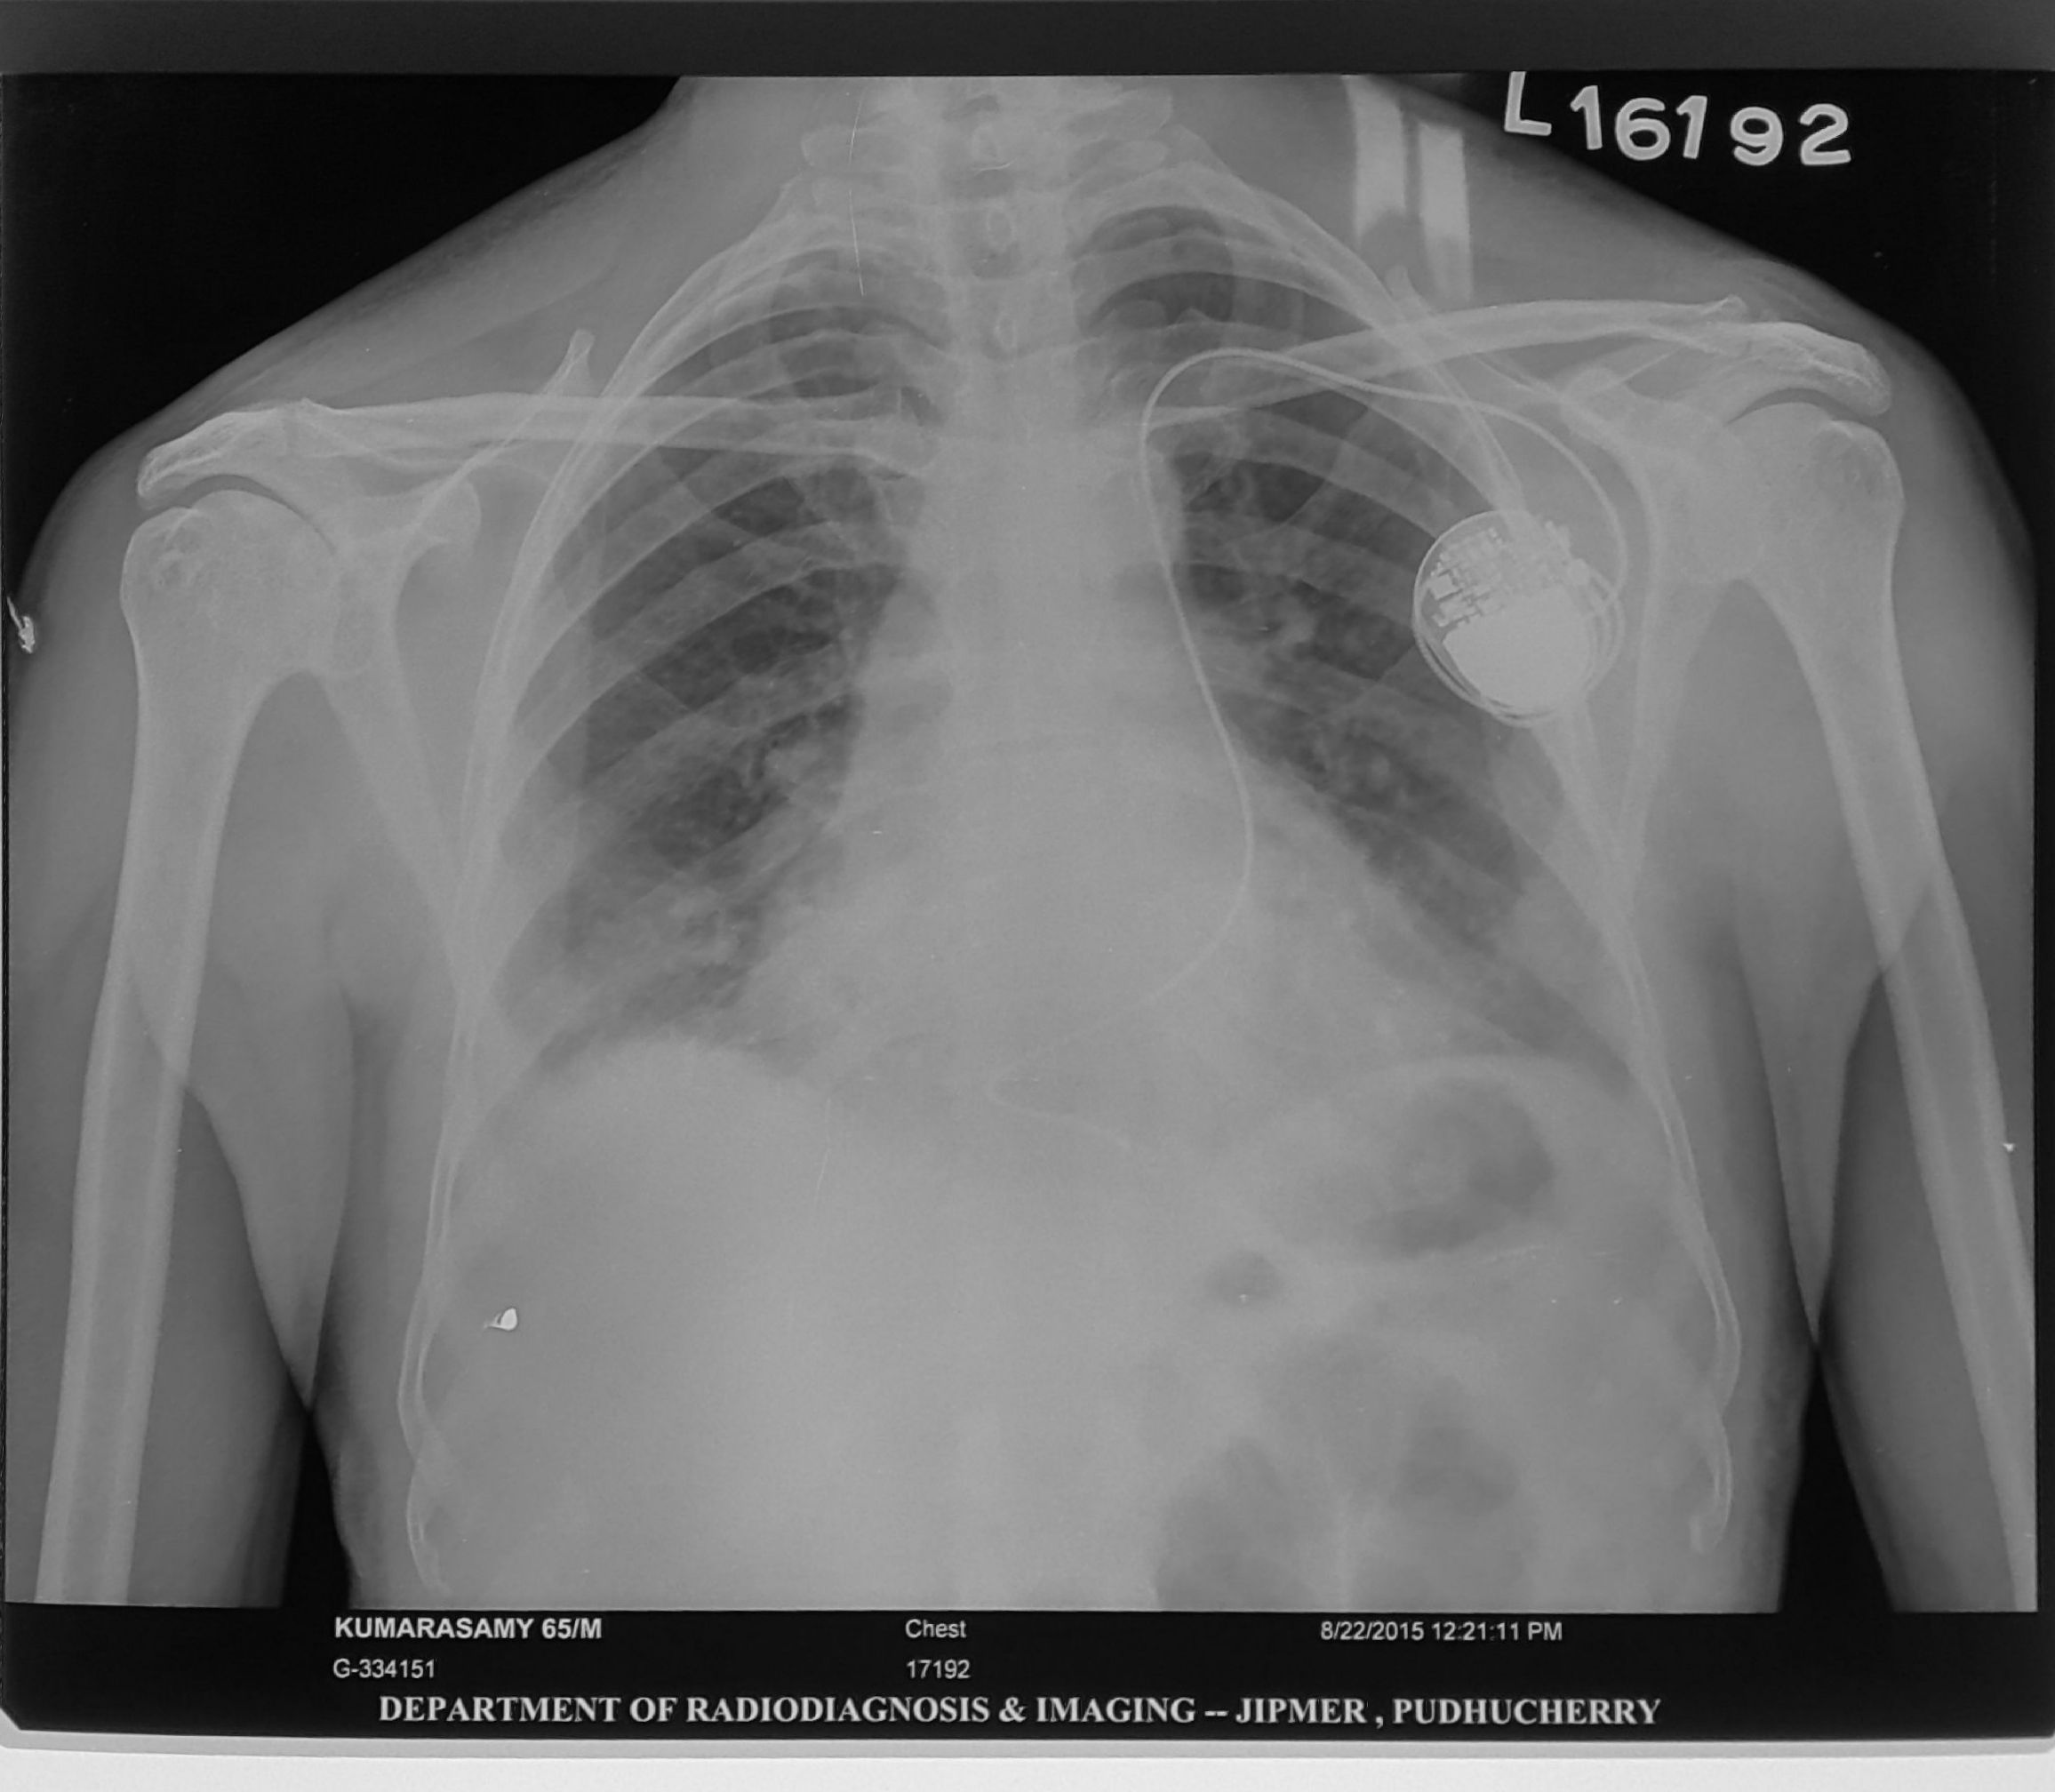

• Chest X ray after 4-6 hours

Post procedure CXR

pneumothorax_post_ppm.jpg